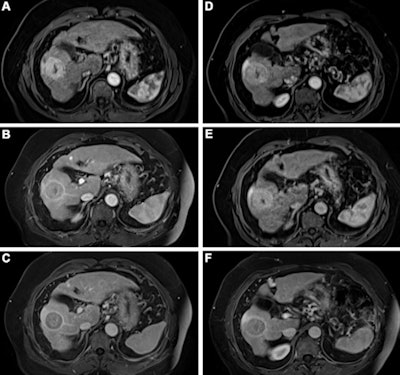

Kuhl's group compared the performance of gadobutrol to gadopiclenol for lesion evaluation via a study that included 260 participants who underwent both gadopiclenol- and gadobutrol-enhanced MRI and had at least one identified lesion. Most patients presented with neoplasms (66%), and the most frequent of these were liver metastases and breast cancer.

The gadopiclenol exam was performed with 0.05 mmol/kg of contrast, while the gadobutrol exam was performed with 0.1 mmol/kg. The exams were read by 18 readers divided into three reading groups to compare the two contrast agents.

The investigators found that gadopiclenol at half the dose of gadobutrol performed comparably for all qualitative visualization parameters and for all readers. The majority of readers across the three groups (ranging from 75% to 83%) reported no preference between the two agents for image quality.